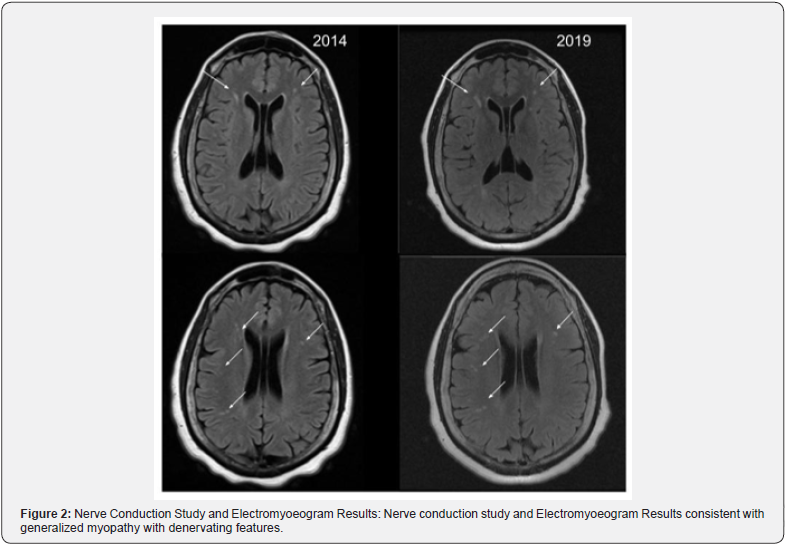

Patient was sent for imaging which showed unchanged white matter lesions without interval radiographic progression for approximately 5 years (as seen in Figure 1). Given low concern for MS, other etiologies were explored and patient was sent for EMG. EMG was consistent with a generalized myopathy with minimal denervating features (Figure 2). Patient was next sent for a muscle biopsy of left deltoid which demonstrated myopathy with lobulated muscle fibers most consistent with Limb Girdle Muscular Dystrophy, suspected to be LGMD2a (Figure 3). Patient was sent for genetic counseling and was established in a neighboring muscular dystrophy clinic.